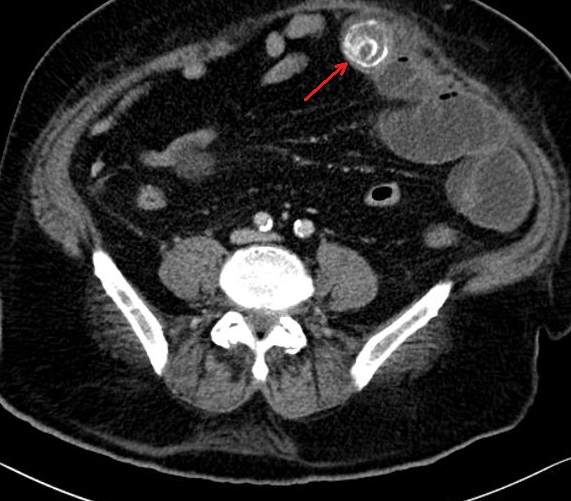

Meme cas en coupe coronal ( frontal ) :

Image de calcul hyperdense se en voyait tres net (

fleche rouge ) avec image de vesicule biliaire

inflamee et la dilatation de canal hepatique commun |